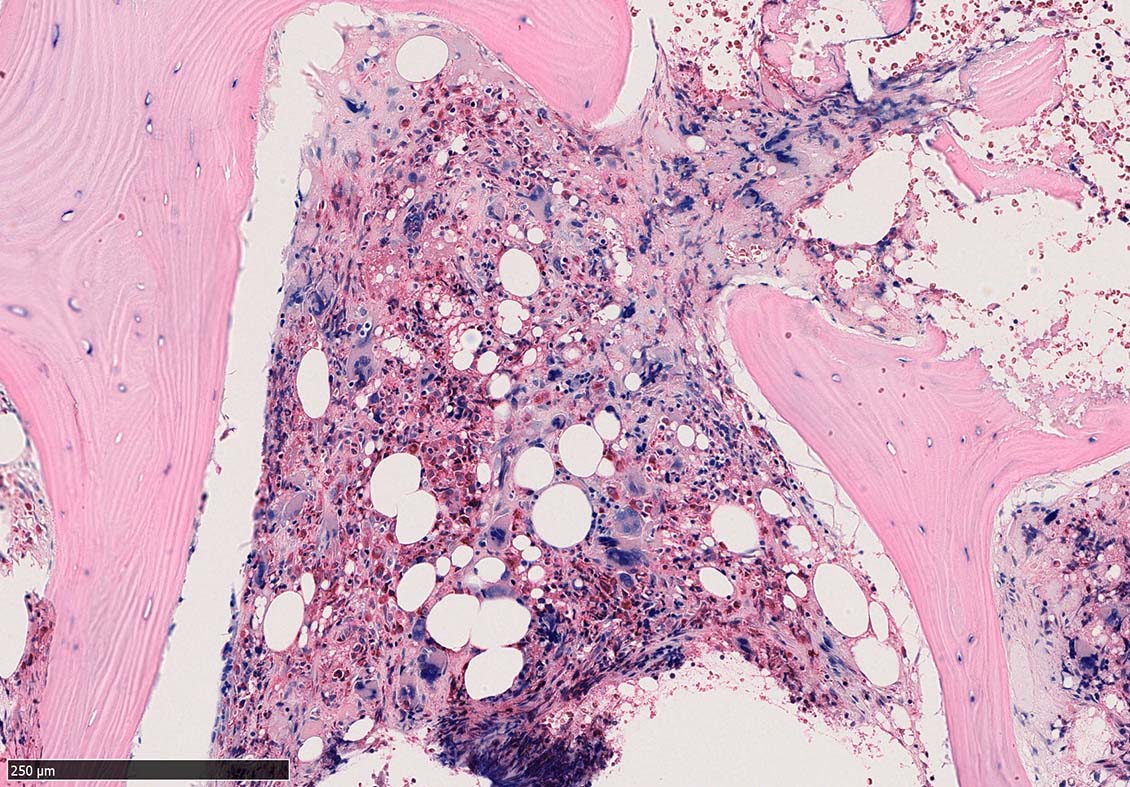

骨髄組織所見 bone marrow biopsy total 6mm in length

Case02; Meylofibrosis, overt fibrosis

77year-old female. 40歳時polycythemia veraと診断されていた.

[注] この症例は詳細は不明であるが, 過去にPVと診断されているため, PVに伴う二次性のmyelofibrosisの診断になる.

黒染する弾性線維の増生のほか, 赤く染まる膠原線維の増生が確認される. MF-2 fibrosis. 鍍銀染色の核染色をすると膠原線維の赤染がわからなくなるので行わない.